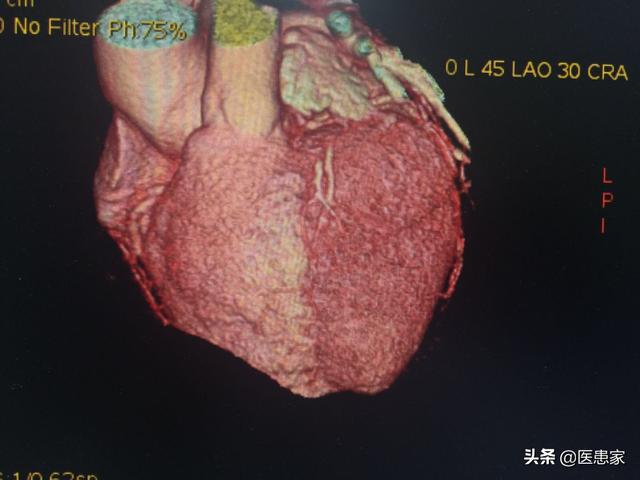

Une aiguille à demeure est placée dans le bras et, lors d'un examen par tomodensitométrie, un agent de contraste est rapidement injecté, qui s'écoulera dans les vaisseaux sanguins du cœur, puis une tomodensitométrie est réalisée et, enfin, une imagerie tridimensionnelle des artères coronaires est effectuée en arrière-plan pour voir s'il y a une sténose des vaisseaux sanguins coronaires et pour juger du degré de sténose. Cependant, cette technique n'est pas aussi précise que la coronarographie en raison de facteurs tels que la coopération, le rythme cardiaque, la respiration, etc. Afin de prévenir la néphropathie de contraste, vous devez boire beaucoup d'eau après l'examen afin d'excréter le produit de contraste le plus rapidement possible. Les personnes dont la fonction rénale est anormale doivent être évaluées par un médecin avant de décider si elles peuvent subir cet examen.

Le changement pathologique de la maladie coronarienne est le rétrécissement de l'artère coronaire dû à la formation d'une plaque d'athérome dans l'artère coronaire. En général, une sténose de l'artère coronaire de plus de 50 % peut être diagnostiquée comme une maladie coronarienne. Le diagnostic de sténose de l'artère coronaire peut être établi par le scanner coronaire et la coronarographie, et l'électrocardiographie peut être utilisée comme test auxiliaire pour l'ischémie myocardique. Parmi ces examens, la coronarographie, qui est l'"étalon-or" du diagnostic des maladies coronariennes, est plus précise. Cependant, comme la coronarographie est un examen invasif qui comporte certains risques et qui est coûteux, de nombreux patients la rejettent.

L'angiographie coronaire peut être réalisée en ambulatoire sans qu'il soit nécessaire de ponctionner une artère ou d'envoyer un cathéter dans le cœur, et convient à certains patients qui ont peur de la coronarographie. La valeur prédictive d'une angiographie coronaire négative est bonne (89,1 %) et celle d'une angiographie positive est de 82,4 %, et il arrive que le résultat de l'angiographie coronaire soit plus lourd qu'il ne l'est en réalité.